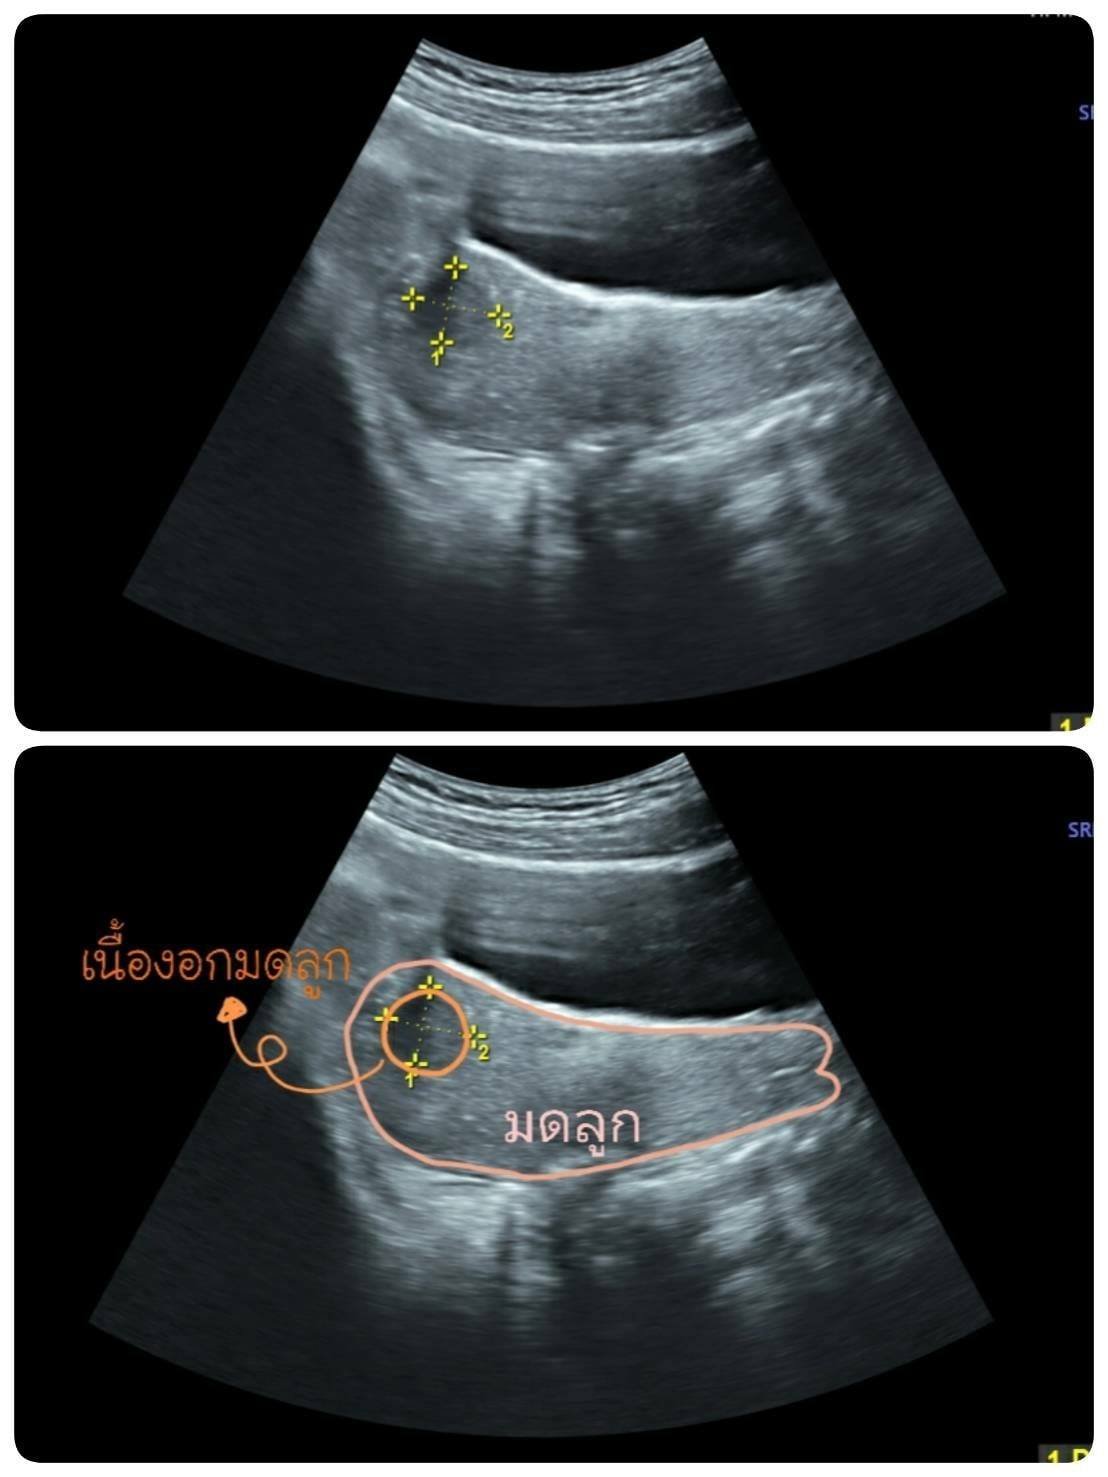

ก้อนเนื้องอกมดลูกที่ตรวจพบจากการอัลตร้าซาวด์ผ่านทางหน้าท้อง